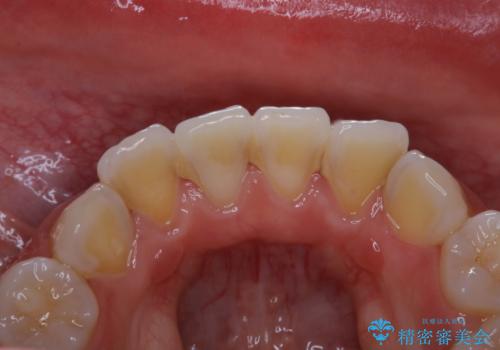

- 子供の頃以来のかなり久しぶりの歯科医院への来院とのことで、プラーク・歯石がべっとり付着していました。

古くからの磨き残しや、歯石などにより、歯肉に炎症がみられ、かなり汚れが多く付着していました。PMTC60分コースで徹底的に汚れをおとしました。施術後の歯肉に出血が見られますが、次第におさまります。